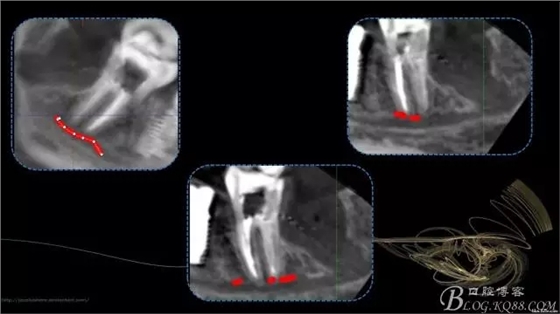

640.webp (2).jpg

640.webp (3).jpg